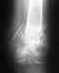

Re: эндопротезирование голеностопного сустава

Действительно, сустав разрушен.